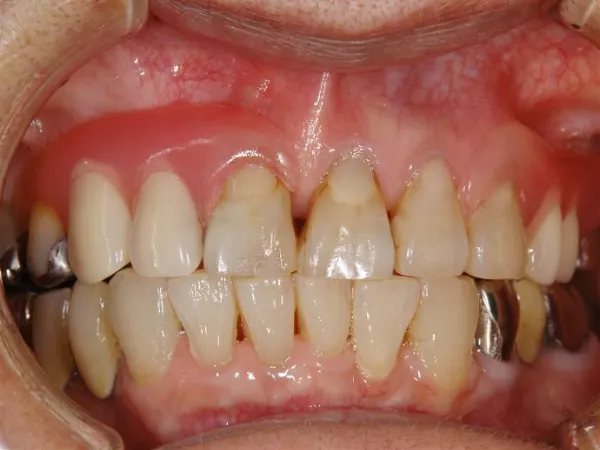

歯の上下や水平な位置関係を確認しながら咬み合わせを調整します。

患者様に快適に使って頂けるように、歯並びや歯の見え方、口の周りのふくらみの様子などをできるだけ細かく確認します。出来上がりの状態に歪みや変形がないかを確認して、最終的に各患者様に合った入れ歯となるよう調整します。